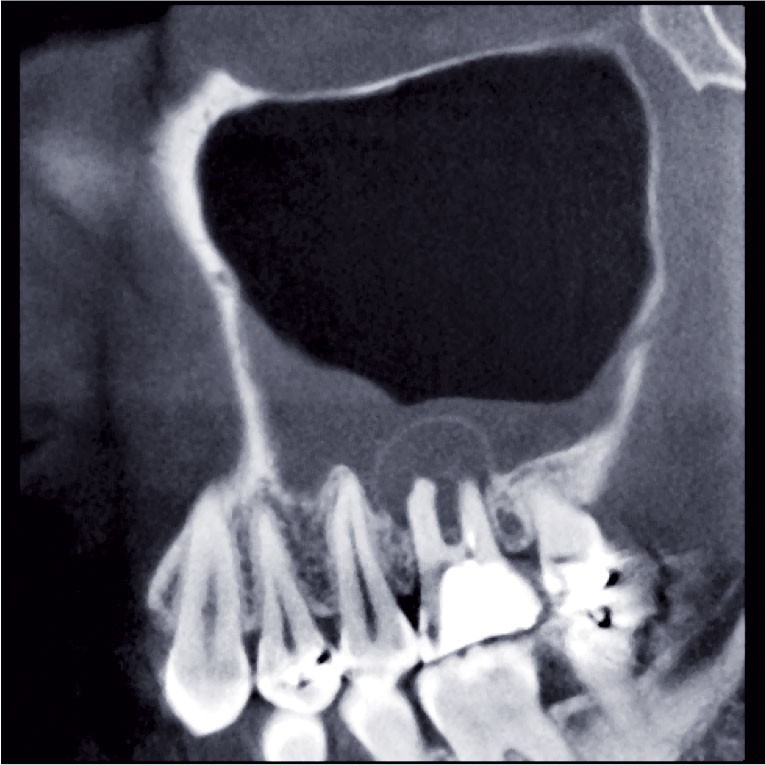

Depuis une dizaine d’années, le CBCT ou « Cone Beam » s’est peu à peu imposé pour l’étude en 3D des dents et des maxillaires à la place de la tomodensitométrie conventionnelle. En effet, cette technique originale d’imagerie volumique numérique a des qualités indéniables tant au niveau de sa résolution spatiale que de sa dosimétrie. Chaque examen doit être correctement adapté, en termes de paramétrages et de champ de vue, à l’indication et aux besoins du prescripteur. Cela nécessite une formation adaptée et une bonne connaissance de l’outil. Au-delà de l’odontologie, le « Cone Beam » est en passe de devenir un examen de référence dans nombre d’explorations de la sphère ORL et maxillo-faciale, sans compter d’autres applications dans des domaines variés, extra-céphaliques.

Le CBCT permet une meilleure compréhension et une meilleure visualisation des pathologies. La précision de l’évaluation morphologique descriptive facilite et améliore le diagnostic, la planification des actes et le pronostic de la pathologie ou du traitement.